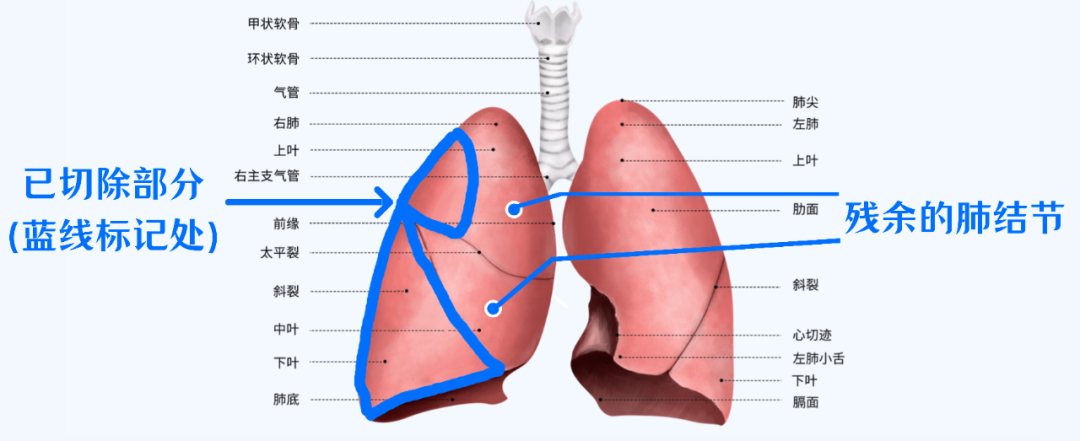

于是,李梅便做了胸腔镜下右肺下叶肺癌根治术+右肺上叶部分切除术(右肺分为上、中、下三叶),最后病理诊断为同时性多原发肺腺癌(右肺下叶主病灶IA期肺腺癌,另一灶原位腺癌,上叶一灶原位腺癌)。

手术切除了一部分肺,右侧余下的两个结节建议随访,暂时未被“清理”。

若再次手术,则需要切除右肺中叶及部分右肺上叶,这样对李梅的身体损伤非常大。